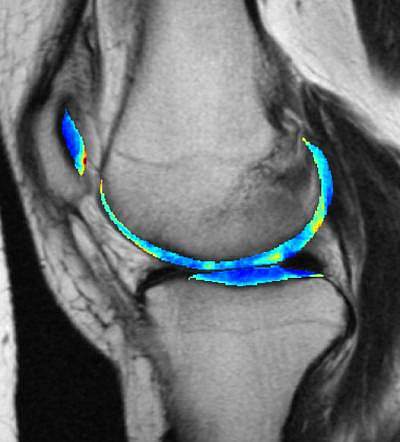

The team used a technique they developed called three-dimensional transport-based morphometry (3D TBM) to identify biochemical changes, such as how much water is present, in cartilage using MRI scans. Using 3D TBM, they analyzed baseline “cartilage maps” of the participants’ knees. After three years, they compared the cartilage maps for the participants who were eventually diagnosed with osteoarthritis with those who were not.

Using machine-learning algorithms, the team trained the system to automatically differentiate between people who would progress to osteoarthritis and those who wouldn’t. The technique detected specific biochemical changes in the center of the knee’s cartilage of those who were pre-symptomatic at the time of the baseline imaging, including decreases in water concentration. The system accurately detected 78% of future osteoarthritis cases.